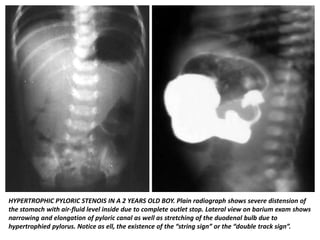

DBMCI Egurukul - ❓Upper GI series demonstrating a narrow and elongated pylorus with a narrow lumen (“string sign”), appearing as puckering of the mucosa (“double track sign”) is a feature of❓ A. The Gastrointestinal String Sign | Radiology Hypertrophic pyloric stenosis- “string sign” | Pediatric surgery, Pediatrics, Radiology Peds in a Pod on X: "If you've listened to Poopcast 3.0, check out this image of the “String sign” for pyloric stenosis. This is a the finding from an UGI, which Hypertrophic pyloric stenosis. ( ) A diagrammatic representation of the... | Download Scientific Diagram Pyloric Stenosis String Sign